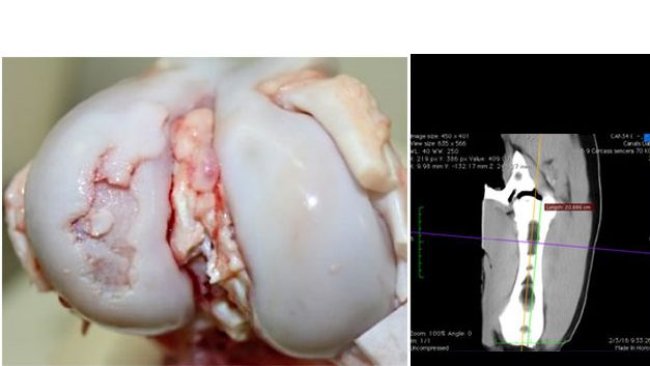

Este artigo revisa o efeito dos componentes da dieta sobre o osso e a osteocondrose, principal causa de claudicação e motivo da eliminação de reprodutores jovens. Portanto, conceitos importantes a serem considerados em dietas de criação de leitoas.